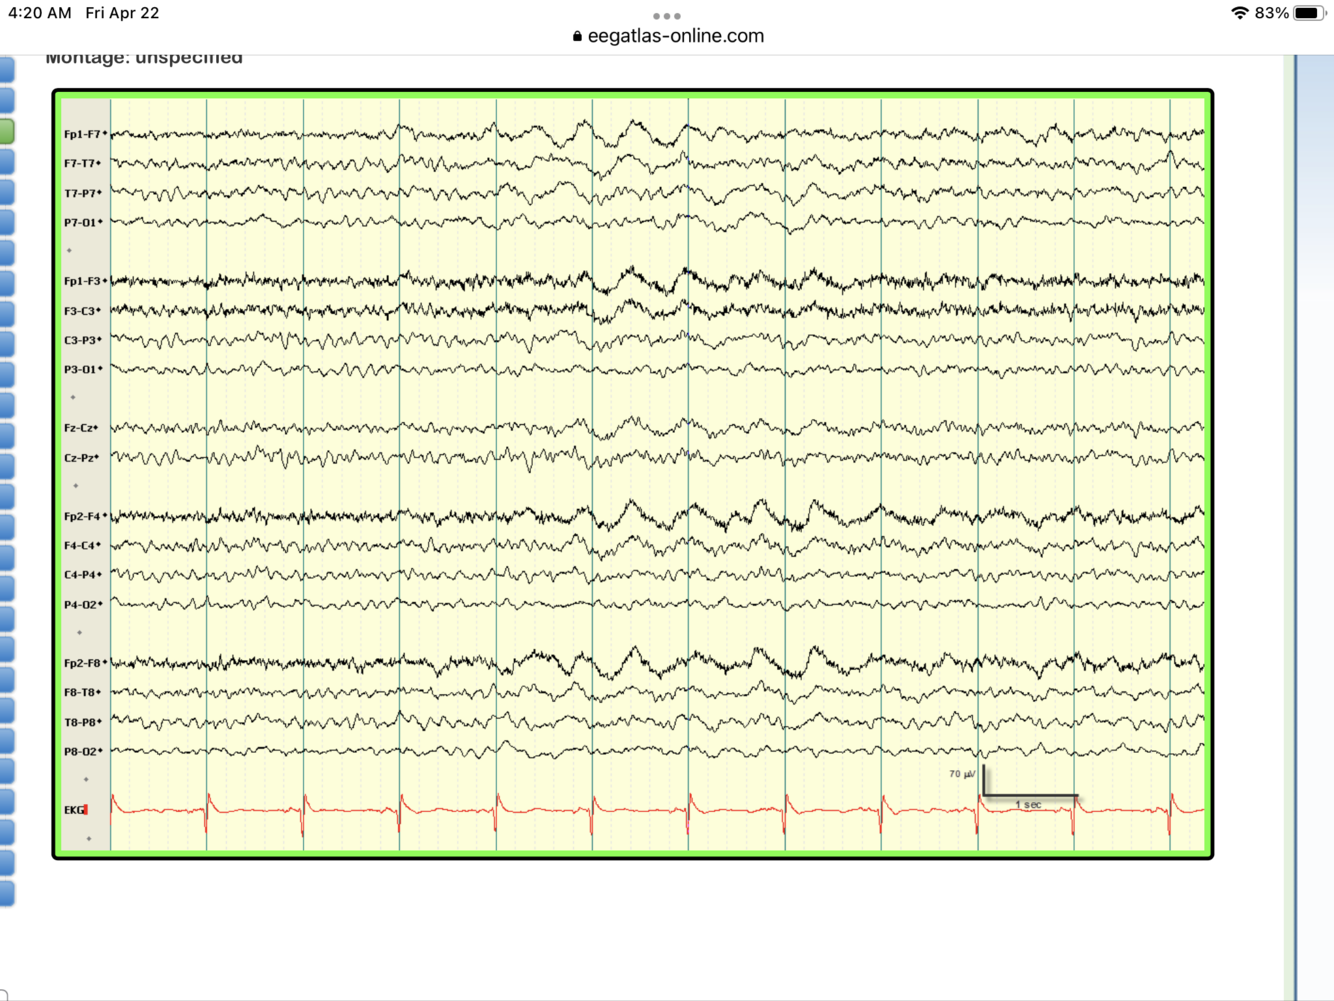

Diagnosis?

PLEDs

seen in subacute strokes, HSV encephalitis, brain abscess or after a run of seizures